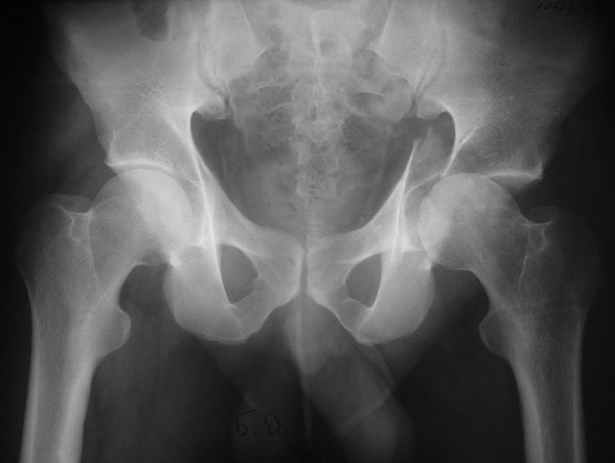

Высылаю пример еще одного случая, остеосинтез пластиной из подвздошного доступа.